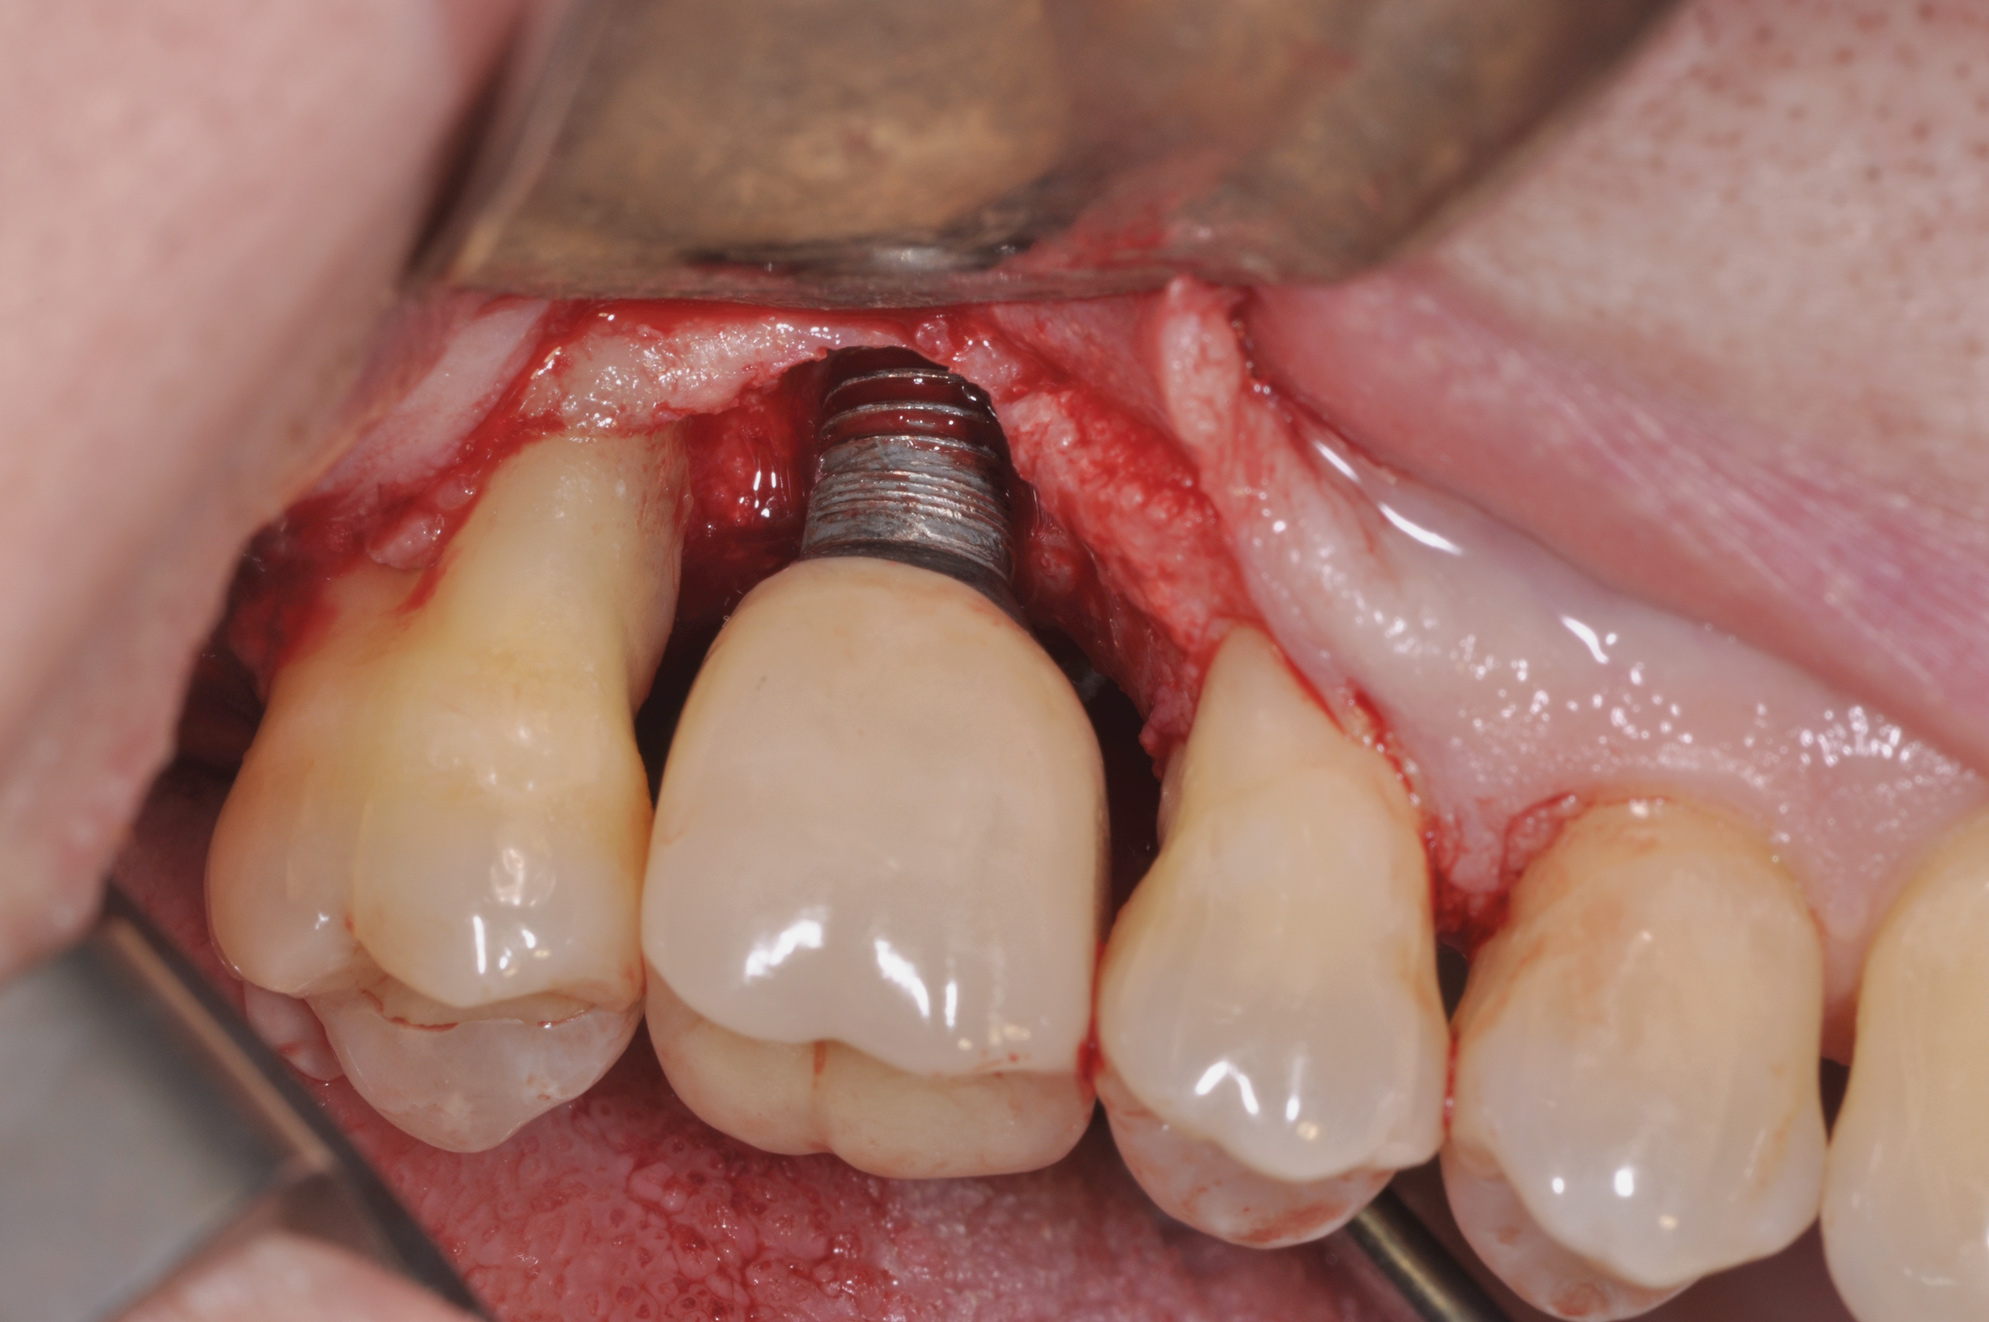

Fig 7. Access flap surgery was performed to assess the defect.

Fig 8. Ostectomy was performed with implant surface modification.